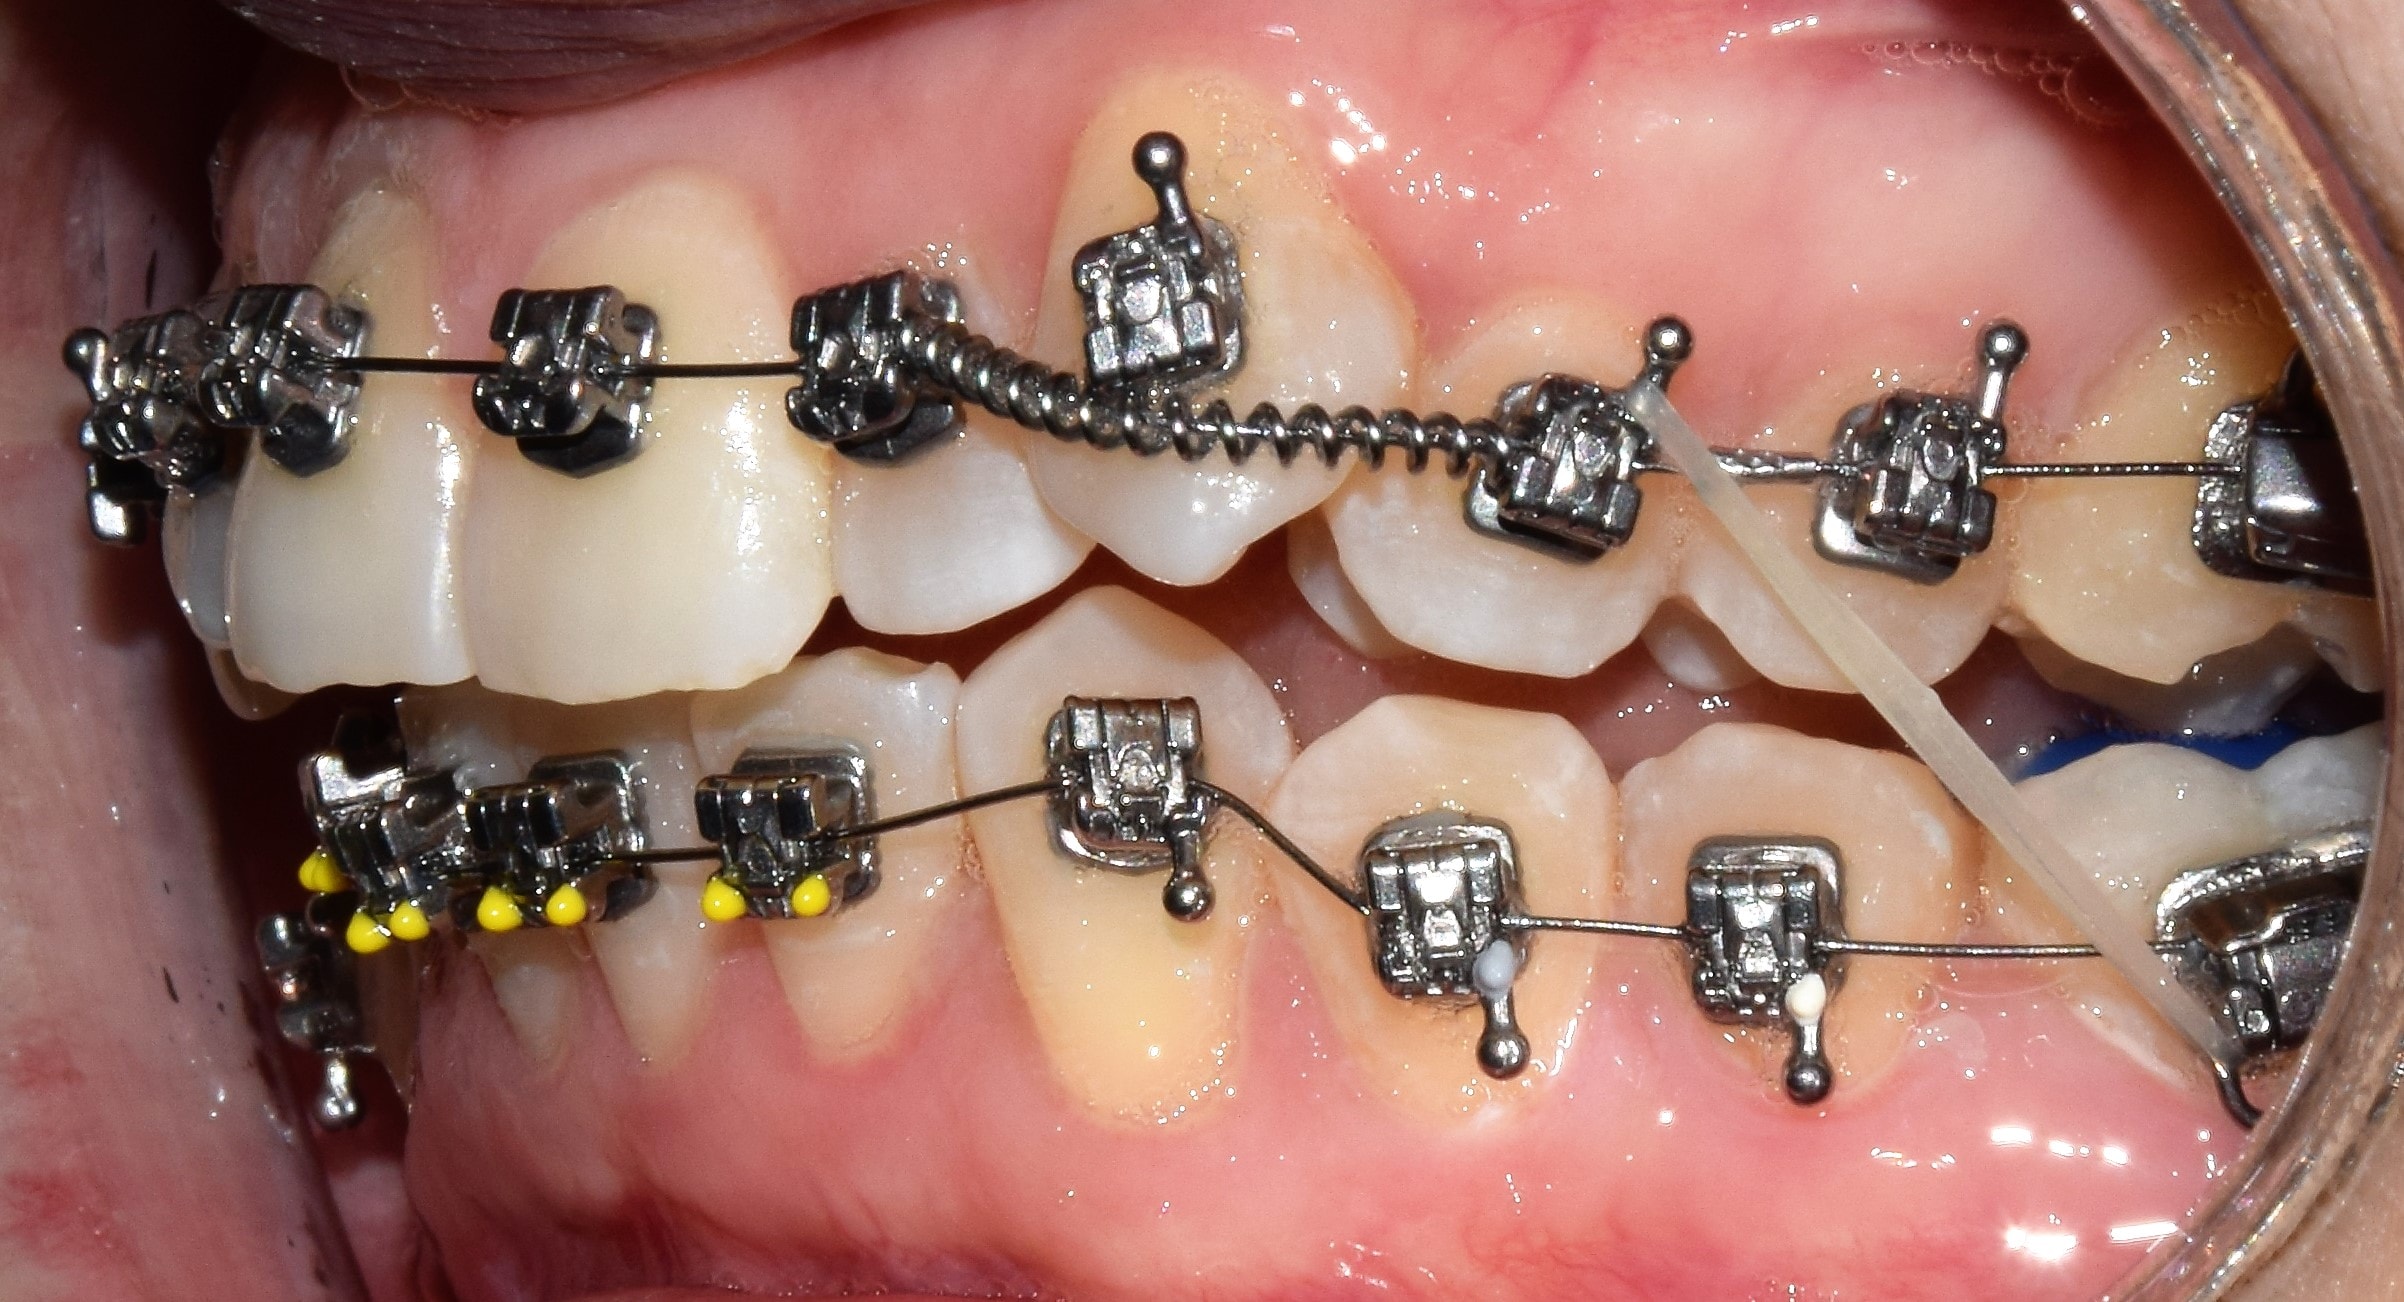

Bracket

Bracketnek nevezzük a rögzített fogszabályzó készülék fogakra ragasztott alkotóelemét, melyekbe a fogszabályzó ívet valamilyen módszerrel rögzítjük. Kisőrlőtől-kisőrlőig dolgozunk bracketekkel, a nagyőrlőkön már tubusok vannak. A bracketek (tappancsok) fogakkal érintkező talpa érdes, hálós szerkezetű, mely jobb rögzülést biztosít. Elsősorban az oldalsó bracketeken (nagyőrlők, kisőrlők, szemfogak), található speciális kampó is. Erre különböző kiegészítő eszközöket akaszthatunk (intermaxilláris gumihúzás, füzérgumi, húzórugó stb.). Anyaga szerint beszélhetünk fém, kerámia, műanyag és arany bracketekről. Az ív rögzítésének típusa szerint megkülönböztetünk hagyományos (az ívet gumival rögzítjük a bracketbe), illetve önligírozó bracketeket (nyitó-záró szerkezettel rögzítjük az ívet).